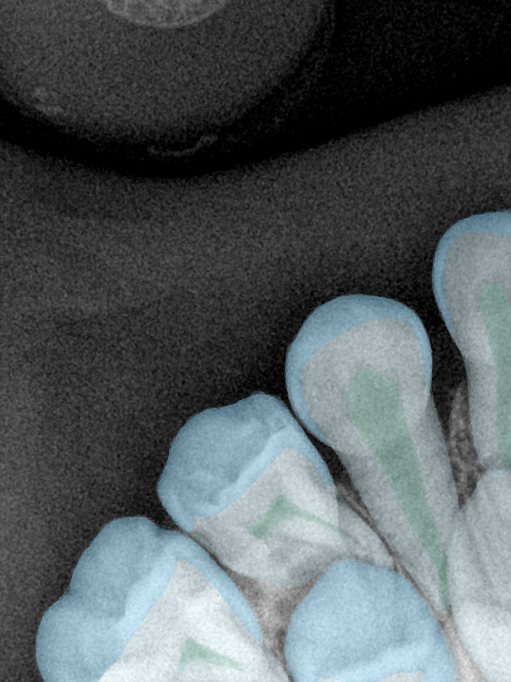

CR/DR 牙齿分割阶段记录

当前进展

- 完成了 CR/DR 牙齿相关分割训练

- 当前结果已经达到阶段预期,但仍有细节问题需要继续处理

相关测试

遇到的问题

- 训练过程中出现过 mask 下移问题

- 部分结果会出现 box 填充异常

- mask 边缘仍然有比较明显的锯齿感

参考

第二版算法问题测试